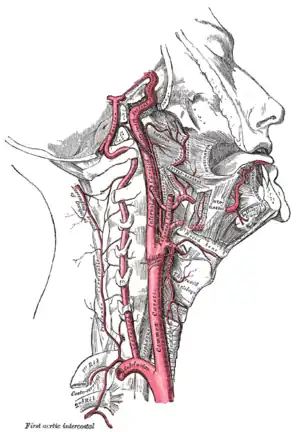

![]() The common carotid artery and its main branches | |

The common carotid arteries are present on the left and right sides of the body. These arteries originate from different arteries but follow symmetrical courses. The right common carotid originates in the neck from the brachiocephalic trunk; the left from the aortic arch in the thorax. These split into the external and internal carotid arteries at the upper border of the thyroid cartilage, at around the level of the fourth cervical vertebra.

At approximately the level of the fourth cervical vertebra, the common carotid artery splits ("bifurcates" in literature) into an internal carotid artery (ICA) and an external carotid artery (ECA). While both branches travel upward, the internal carotid takes a deeper (more internal) path, eventually travelling up into the skull to supply the brain. The external carotid artery travels more closely to the surface, and sends off numerous branches that supply the neck and face.

When the sternocleidomastoid muscle is drawn backward, the artery is seen to be contained in a triangular space known as the carotid triangle. This space is bounded behind by the sternocleidomastoid, above by the stylohyoid and the posterior belly of the digastric muscle, and below by the superior belly of the omohyoid.